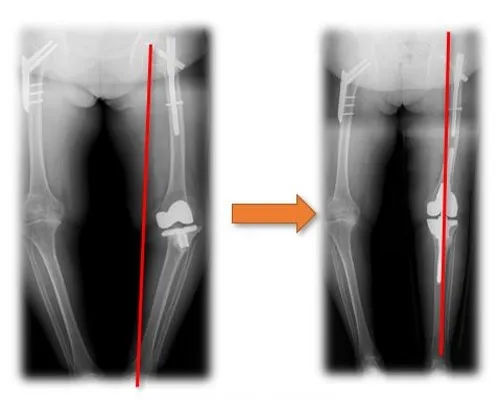

Solution for Osteoarthritis Secondary to Hip Dysplasia